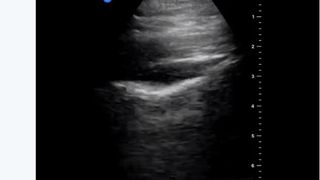

„Ziua 1 după ce am fost diagnosticat cu COVID-19. Durere în gât, durere de cap puternică, tuse seacă, dar fără dificultate respiratorie. Fără anormalități la plămâni, la ecografie”, a scris el, în primul astfel de mesaj.